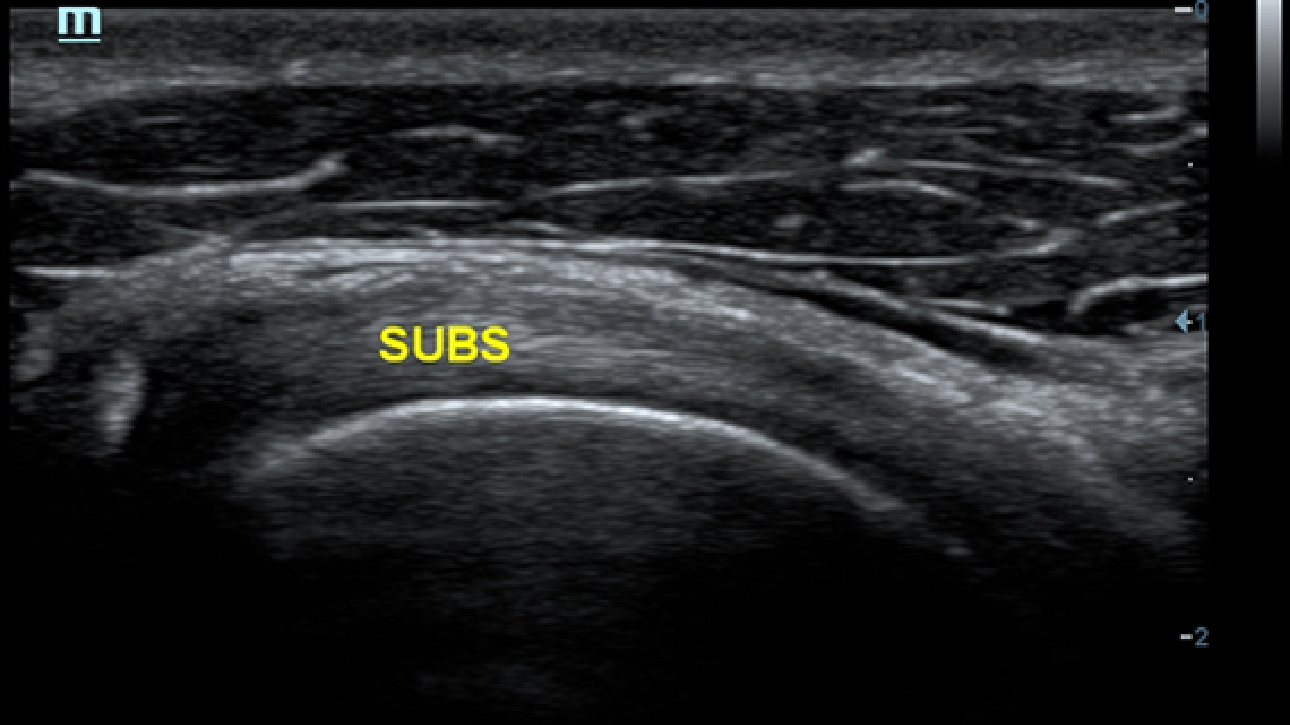

eXceeding Experience

Esperienza ad alta produttivit├Ā